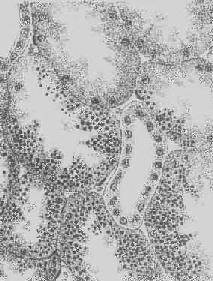

肝淀粉样变

图1-22 肝淀粉样变

淀粉样物质呈均质状,沉着于窦内皮下,肝细胞索受压萎缩